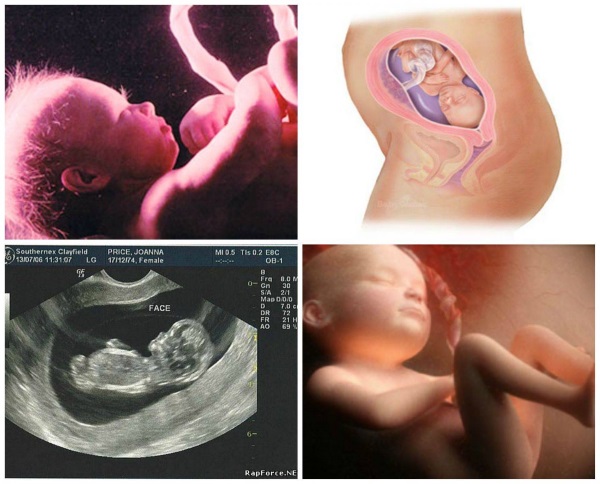

На 27-й неделе беременности плод активно растет и готовится к жизни вне материнского организма. В этот период его вес достигает примерно 900 граммов, а рост составляет 36-38 сантиметров. Специалисты отмечают, что завершается формирование всех основных систем органов, а кожа плода начинает приобретать розоватый оттенок благодаря накоплению подкожного жира. Женщина может испытывать различные ощущения: от увеличения активности плода до дискомфорта в области живота из-за растяжения связок. УЗИ на этом сроке позволяет наблюдать за активными движениями малыша, а также оценить его положение и развитие. Врачи советуют будущим мамам больше отдыхать и внимательно следить за своим состоянием, поскольку эмоциональное и физическое здоровье играют ключевую роль в успешном течении беременности.

На УЗИ в этот срок можно увидеть, как ребенок уже принимает различные позы, а его лицо начинает приобретать узнаваемые черты. Многие женщины отмечают, что в это время у них усиливаются эмоциональные переживания, что связано с гормональными изменениями и подготовкой к родам. Важно, чтобы будущая мама продолжала следить за своим состоянием, правильно питалась и посещала врача для регулярных осмотров.

| Развитие рефлексов: У ребенка развиты сосательный, глотательный и хватательный рефлексы. | Учащенное мочеиспускание: Давление матки на мочевой пузырь приводит к более частому мочеиспусканию. | Фото на УЗИ: На УЗИ можно увидеть хорошо сформированное лицо ребенка, его активные движения, а также оценить состояние плаценты и количество околоплодных вод. |

УЗИ на 27-й неделе: На ультразвуковом исследовании на этом сроке можно увидеть, как формируются черты лица малыша, а также оценить его рост и развитие. УЗИ может показать, как плод занимает положение в матке, что важно для предстоящих родов.

На 27-й неделе беременности женщина начинает замечать значительные изменения как в своем теле, так и в эмоциональном состоянии. Плод активно растет: его размер сопоставим с цветной капустой, и он уже способен реагировать на свет и звуки. УЗИ на этом этапе позволяет увидеть движения малыша и определить его пол, если родители еще не знают. Многие женщины отмечают, что их живот становится более округлым, и они начинают ощущать легкие толчки и шевеления, что приносит радость и волнение. Однако могут возникать и некоторые неудобства, такие как боли в спине или отеки. Важно внимательно следить за своим состоянием и регулярно посещать врача, чтобы убедиться, что все идет хорошо. Этот период наполнен ожиданием и подготовкой к встрече с новым членом семьи.

На 27-й неделе беременности (развитие плода можно оценить с помощью ультразвукового исследования, которое рекомендуется проходить по назначению врача) наблюдается практически полное формирование систем в организме ребенка. Единственным органом, который еще не готов к функционированию, остаются легкие, так как они продолжают развиваться.

Снимки УЗИ на 27 неделе

Ультразвуковое исследование беременной женщине на 27 неделе врач гинеколог назначает, если подозревает развитие серьезной патологии. Результаты обследования помогут установить точный диагноз.

Снимки дополнительно позволяют определить следующие характеристики:

- состояние матки;

- расположение плода;

- сердечный ритм крохи;

- количество и качество околоплодных вод;

- зрелость плаценты;

- развитие плода.

Если специалист на ультразвуковом исследовании обнаружил отклонения, женщине назначают допплер маточных и пуповинных артерий.

На УЗИ на 27 неделе беременности можно увидеть развитие плода, его размеры, положение в матке, а также оценить состояние плаценты и околоплодных вод. Врач может проверить сердечный ритм плода, его движения и анатомические особенности, такие как форма головы, наличие конечностей и органов. Также возможно выявление некоторых аномалий или патологий, если они имеются.